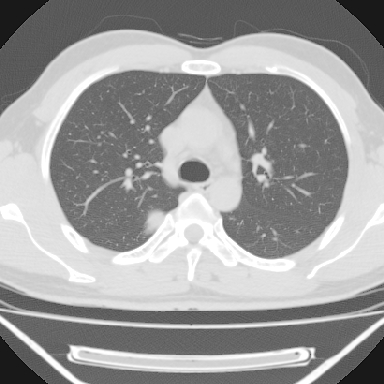

标题: CT6237:右上后纵隔旁肿块影

m 30 右胸痛10年

右上后纵隔脊柱旁类圆形肿块,边界光整,与胸腔呈钝角,首先考虑来源于肺外,神经源性肿瘤(神经鞘瘤可能大,神经鞘瘤)

右上后纵隔旁软组织肿块影,与肺界面光滑,与胸壁呈钝角相交,提示肺外病变。位于肋骨下缘,边缘清楚,呈三角样指向与右侧椎间孔,但并示进入椎间孔;与对侧神经根对比,属同一走行方向。

考虑后纵膈良性肿瘤,神经源性肿瘤可能大。

右上后纵隔脊柱旁类圆形肿块,边界光整,与胸腔呈钝角,首先考虑来源于纵膈,神经源性肿瘤可能大。

右上后纵隔脊柱旁见长椭圆形肿块,边界光整,与胸壁呈钝角。周围骨质未见异常。

考虑、1、后纵隔神经源性肿瘤;

2、不除外单发胸膜间皮瘤。

右上后纵隔脊柱旁类圆形肿块,边界光整,与胸膜呈钝角,首先考虑来源于肺外,神经源性肿瘤(神经纤维瘤可能大)。